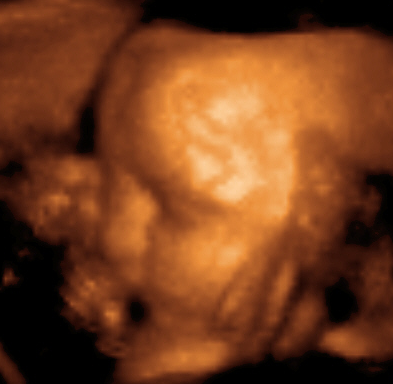

Okres płodowy rozpoczyna się wraz z nadejściem 9 tygodnia życia wewnątrzmacicznego i trwa do końca ciąży. Na początku tego okresu płód ma około 33 mm długości. W okresie płodowym dochodzi do dojrzewania i rozwoju narządów powstałych podczas organogenezy w okresie zarodkowym.

Twarz zaczyna się formować około 4 tygodnia życia zarodka. W 8 tygodniu dochodzi do pełnego wykształcenia twarzoczaszki – zaczyna ona powoli przypominać twarz noworodka.